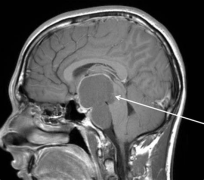

INC德国Schroeder教授关于神经内镜经鼻入路治疗颅咽管瘤的解析 INC国际神经外科医生集团、国际神经内镜联合会执行委员会主席Henry W. S. Schroeder教授关于神经...

INC旗下国际神经外科顾问团(WANG)专家成员James T. Rutka教授在论文中表示:了解鞍区和鞍上区解剖是选择颅咽管瘤较好手术入路的关键...

颅内颈动脉位于视神经的外侧。颈动脉常突出于蝶窦外侧壁,视神经管突出于蝶窦上外侧,三叉神经二分支突出于蝶窦下外侧。视神经、动眼神经、颈动脉...